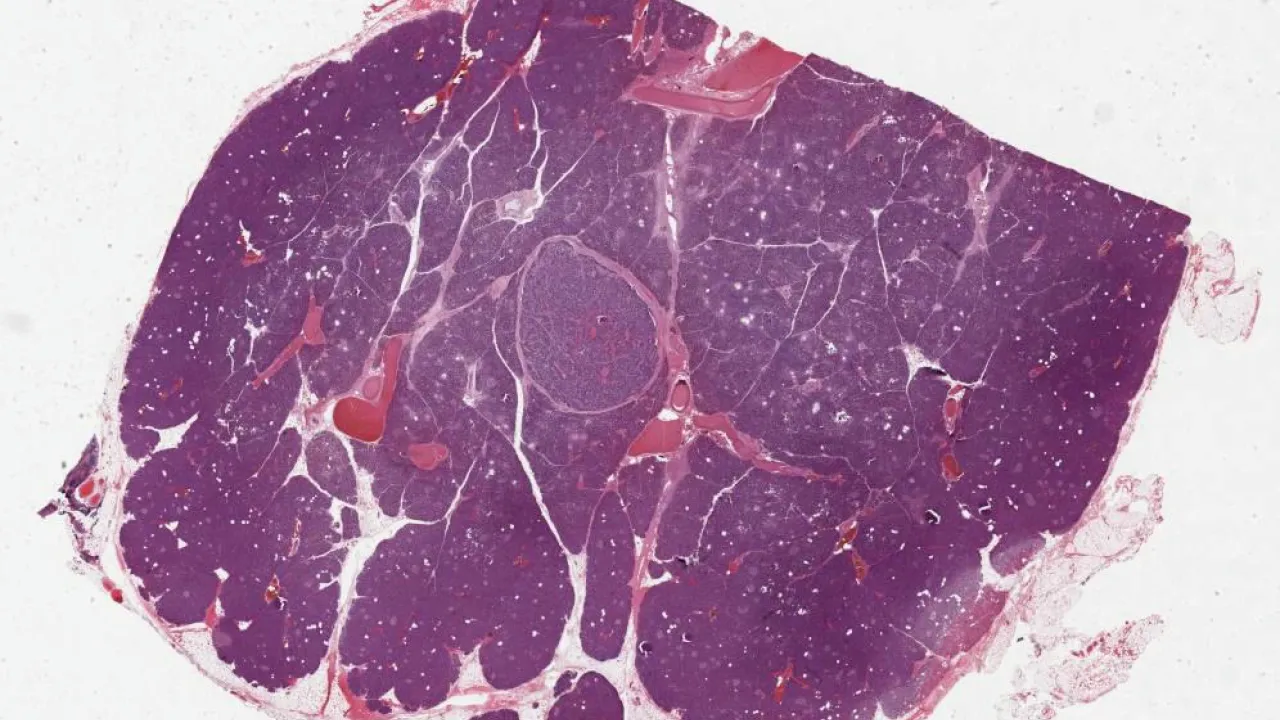

Pancreas, Pancreatic neuroendocrine tumour, low grade, H&E stain